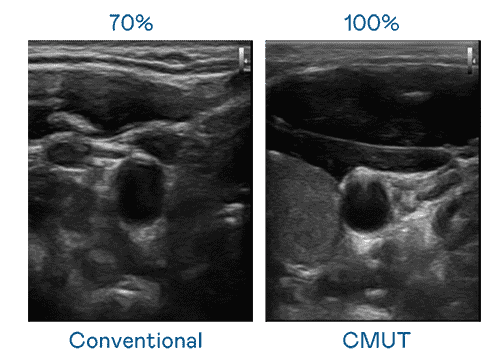

CMUT 技术是一种用电容式微机电元件来产生超音波讯号的技术。。。。与传统 PZT 压电式技术相比,,,CMUT 频宽增加 30%,,,,更宽频的超音波讯号让影像解析度大幅提升,,是实现高影像品质医疗超音波扫描、、、促进精准医疗发展的关键技术。。。

大频宽带来超清晰影像

超音波影像的解析度高低,,首先取决于探头能发出的讯号频宽。。。口袋牛店 CMUT 可提供高清晰的超音波讯号,,,提供高频宽、、、、高灵敏度、、、、影像纹理细节更高的超音波影像,,,协助医护人员缩短影像判读时间及利用精准的医疗影像进行诊断。。